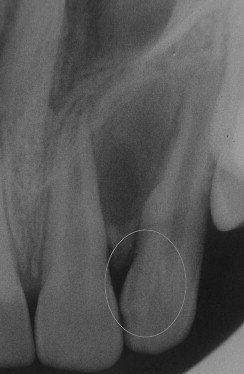

Diagnosis of this tooth?

Turner’s hypoplasia

What causes Turner’s hypoplasia?

A periapical inflammatory disease of the primary dentition causes hypoplasia of the underlying, developing deciduous tooth.